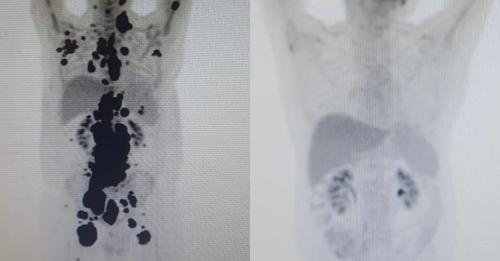

“Foi uma resposta muito rápida e com tanto tumor. Fico até emocionado [ao ver as duas ressonâncias de Paulo]. Fiquei muito surpreso de ver a resposta, porque a gente tem que esperar pelo menos um mês depois da infusão da célula. Quando a gente viu, todo mundo vibrou. Coloquei no grupo de professores titulares da USP e todo mundo impressionado de ver a resposta que ele teve”, comemorou o especialista.

Antes e depois

As duas imagens do Pet Scan (tomografia feita com um contraste especial ) (veja acima) representam “dois Paulos”: a da esquerda, o paciente que tinha como caminho único os cuidados paliativos, quando a alternativa é dar conforto, mas já sem expectativa de cura, e a da direita, um paciente com um organismo já sem tumores após o tratamento com CAR-T Cell.

“A vitória não é só minha. É da fé, da ciência e da energia positiva das pessoas. Cada uma delas ajudou a colocar um paralelepípedo nesse caminho. A imagem prova com muita clareza para qualquer pessoa a gravidade do meu linfoma, e eu não tinha ideia de que era assim”, contou o paciente.